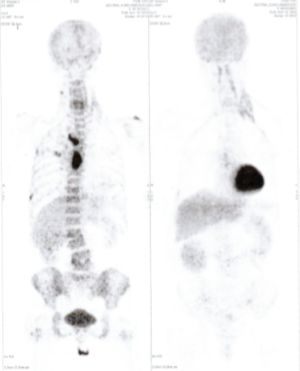

CASE NO: 3 (PROSTATE CANCER)

A middle-aged man with castration resistant prostate cancer, having failed all currently available cancer treatment, was very weak, and getting worse every day. The PET/CT scan showed he had massive bone metastases. After a few treatment, all the bone metastases went into remission. About 6 months later, he is still in remission.

CASE NO: 4 (PROSTATE CANCER)

A middle-aged man with castration resistant prostate cancer and massive bone metastases, failed all currently available cancer treatment, including with the new and expensive drug XTANDI. After a few treatment, most of the bone metastases went into remission, and the remaining ones are less active. Treatment will continue. Cases no: 3 and 4 show that terminal prostate cancer today can be cured with our new cancer treatment.